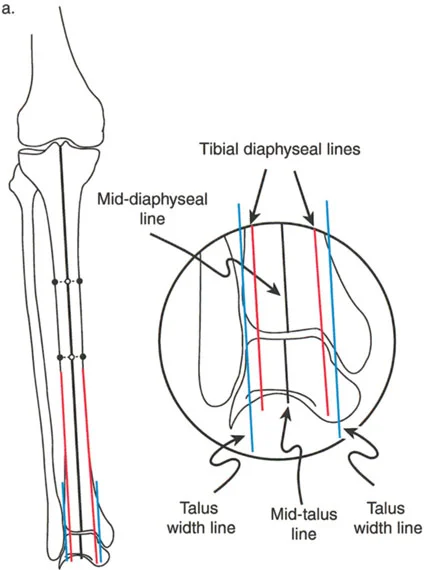

يُعد التقوس الخلفي بعد الصدمة نتيجة متكررة لكسور هضبة الظنبوب الشديدة وعالية الطاقة (مثل كسور شاتزكر V أو VI). في هذه الإصابات، يتم "سحق" الهضبة المفصلية على الجزء الميتافيزي، وتلتئم في حالة منخفضة، بينما تظل الحدبة الظنبوبية متصلة بالجزء الأمامي البعيد.

في هذه الحالات الصعبة، قد يظهر المريض بمعايير إشعاعية شديدة. ليس من غير المألوف رؤية فرط استقامة سريري بمقدار 9 درجات أو أكثر، وزاوية PPTA غير طبيعية بشكل كبير تبلغ 108 درجات، وزاوية PDFA طبيعية نسبياً تبلغ 85 درجة.

غالباً ما يكشف الفحص السريري والإشعاعي عن تشوه لافت: تبرز الحدبة الظنبوبية بشكل واضح في مفصل الركبة الأمامي، وتعمل كعائق عظمي مادي للتمدد الكامل. علاوة على ذلك، يقع الجزء الخلفي من لقمتي الظنبوب بعيداً خلف لقمتي الفخذ، مما يؤكد الخلع الجزئي الخلفي المزمن.

تقنية قطع العظم على شكل حرف L

لتصحيح هذا التشوه المعقد، متعدد المستويات داخل المفصل والميتافيزي، فإن قطع العظم المستعرض القياسي غير كافٍ. تُعد تقنية قطع العظم على شكل حرف L هي الإجراء المفضل.

- التصميم: يتم تصميم قطع العظم بدقة لفصل الكتلة المفصلية المنخفضة عن الحدبة الأمامية. يمتد الجزء العمودي من "L" خلف الحدبة، بينما يمتد الجزء الأفقي أسفل الهضبة المنخفضة.

- التنفيذ: يسمح هذا للجراح برفع الكتلة المفصلية المنخفضة للأعلى وإمالتها للأمام، مع إعادة وضع الحدبة الظنبوبية إلى موقعها التشريحي بالنسبة لخط المفصل في نفس الوقت.

- التثبيت: يتيح استخدام جهاز إليزاروف أو إطار دائري سداسي الأرجل تصحيحاً تدريجياً ومتحكماً للتقوس الخلفي. توفر الأسلاك الدقيقة تثبيتاً ممتازاً في الجزء المفصلي القريب الصغير.

- النتيجة: استعادة كاملة لزاوية PPTA، وتقليل تشريحي للمفصل الظنبوبي الفخذي، وتطبيع مستوى إدخال وتر الرضفة.

تُظهر الصورة تخطيطاً لقطع العظم على شكل حرف L، وهي تقنية معقدة تستخدم لتصحيح التقوس الخلفي بعد كسور هضبة الظنبوب.

تُظهر هذه الصورة نتائج جراحة قطع العظم على شكل حرف L، مع استعادة المحاذاة التشريحية للركبة.